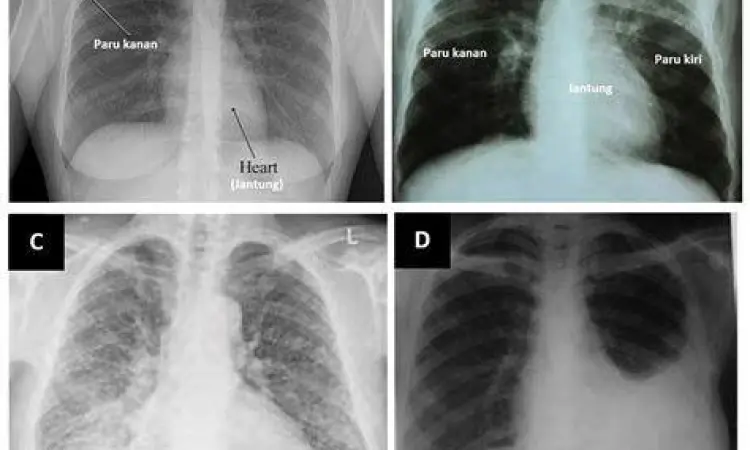

Jika Anda merasakan adanya ciri ciri tbc pada diri sendiri atau kerabat, jangan menunda untuk melakukan pemeriksaan medis. Dokter biasanya akan melakukan serangkaian tes seperti Tes Cepat Molekuler (TCM), rontgen dada, dan tes darah. Pengobatan TBC bukanlah hal yang instan. Pasien diwajibkan mengonsumsi kombinasi antibiotik selama minimal 6 hingga 9 bulan tanpa terputus.